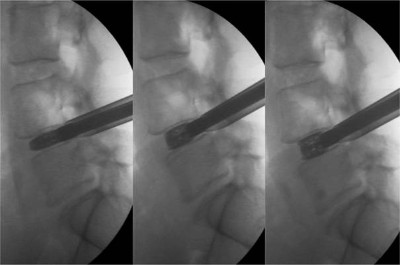

Imágenes fluoroscópicas de la inserción del implante expandible en un disco colapsado y su expansión progresiva restaurando la altura original del disco intervertebral (de izquierda a derecha)